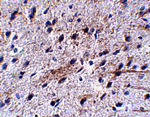

Immunohistochemistry of LRFN5 in mouse brain tissue with LRFN5 antibody at 5 ug/mL.